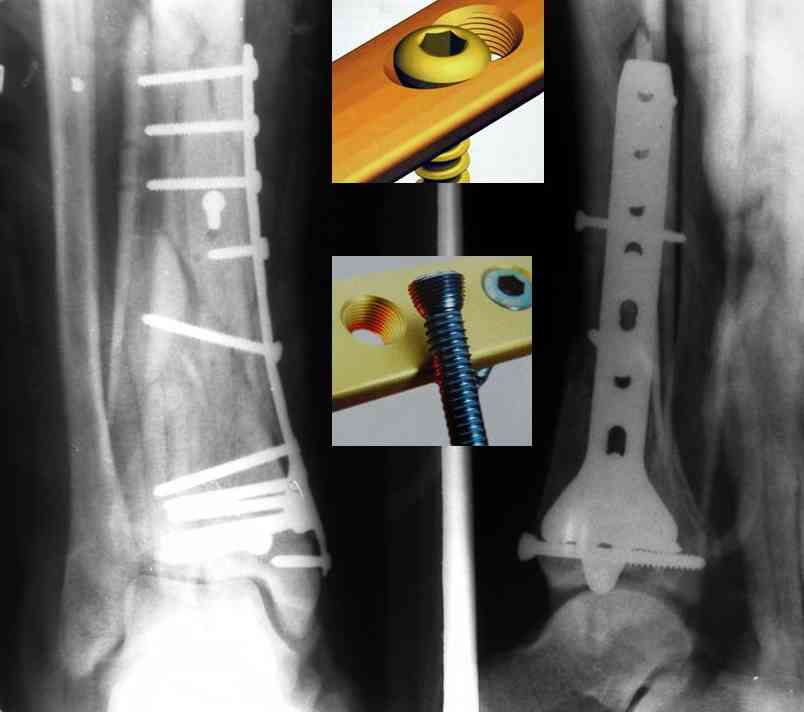

Кстати, при переломах переднего края по классификации АО В-3 при переломах пилона пластина укладывается по передней поверхности. Она достаточно тонкая и эластичная, не надо этого бояться. Посылаю три снимка.